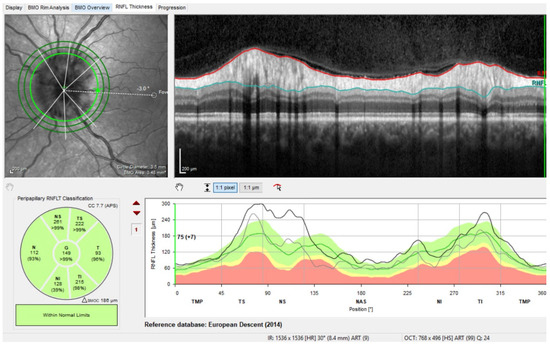

The Minimum Rim Width (MRW)

- Influence of the optic disc size on the MRW:

The Retinal Nerve Fiber Layer (RNFL)

- Influence of refraction on the RNFL:

- Influence of ethnicity: